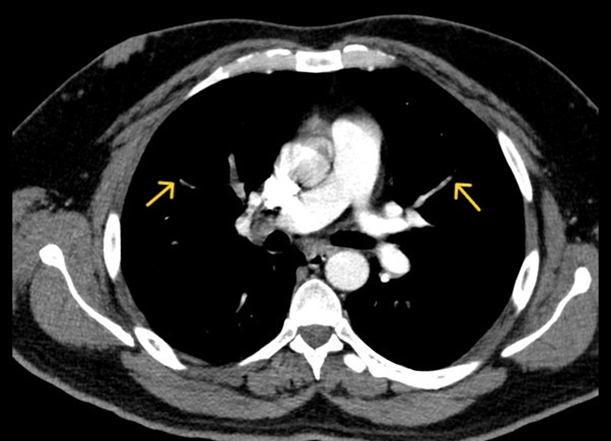

Initial laboratory evaluation revealed elevated levels of D-dimer, total creatine kinase (CK), and lactate dehydrogenase (LDH) (Table 1). Given the elevated D-dimer in the context of pleuritic chest pain and recent long-haul travel, an urgent computed tomography pulmonary angiogram (CTPA) was performed (Figure 1), which confirmed the presence of multiple pulmonary emboli. The patient was promptly initiated on therapeutic anticoagulation therapy with low-molecular-weight heparin (LMWH), which was subsequently transitioned to rivaroxaban, a direct oral anticoagulant. The patient was closely monitored during follow-up and demonstrated clinical improvement.

Figure 1: CT pulmonary angiogram showing filling defects in second and third generation branches of both lungs indicating bilateral lower lobe pulmonary embolism (Yellow arrows)